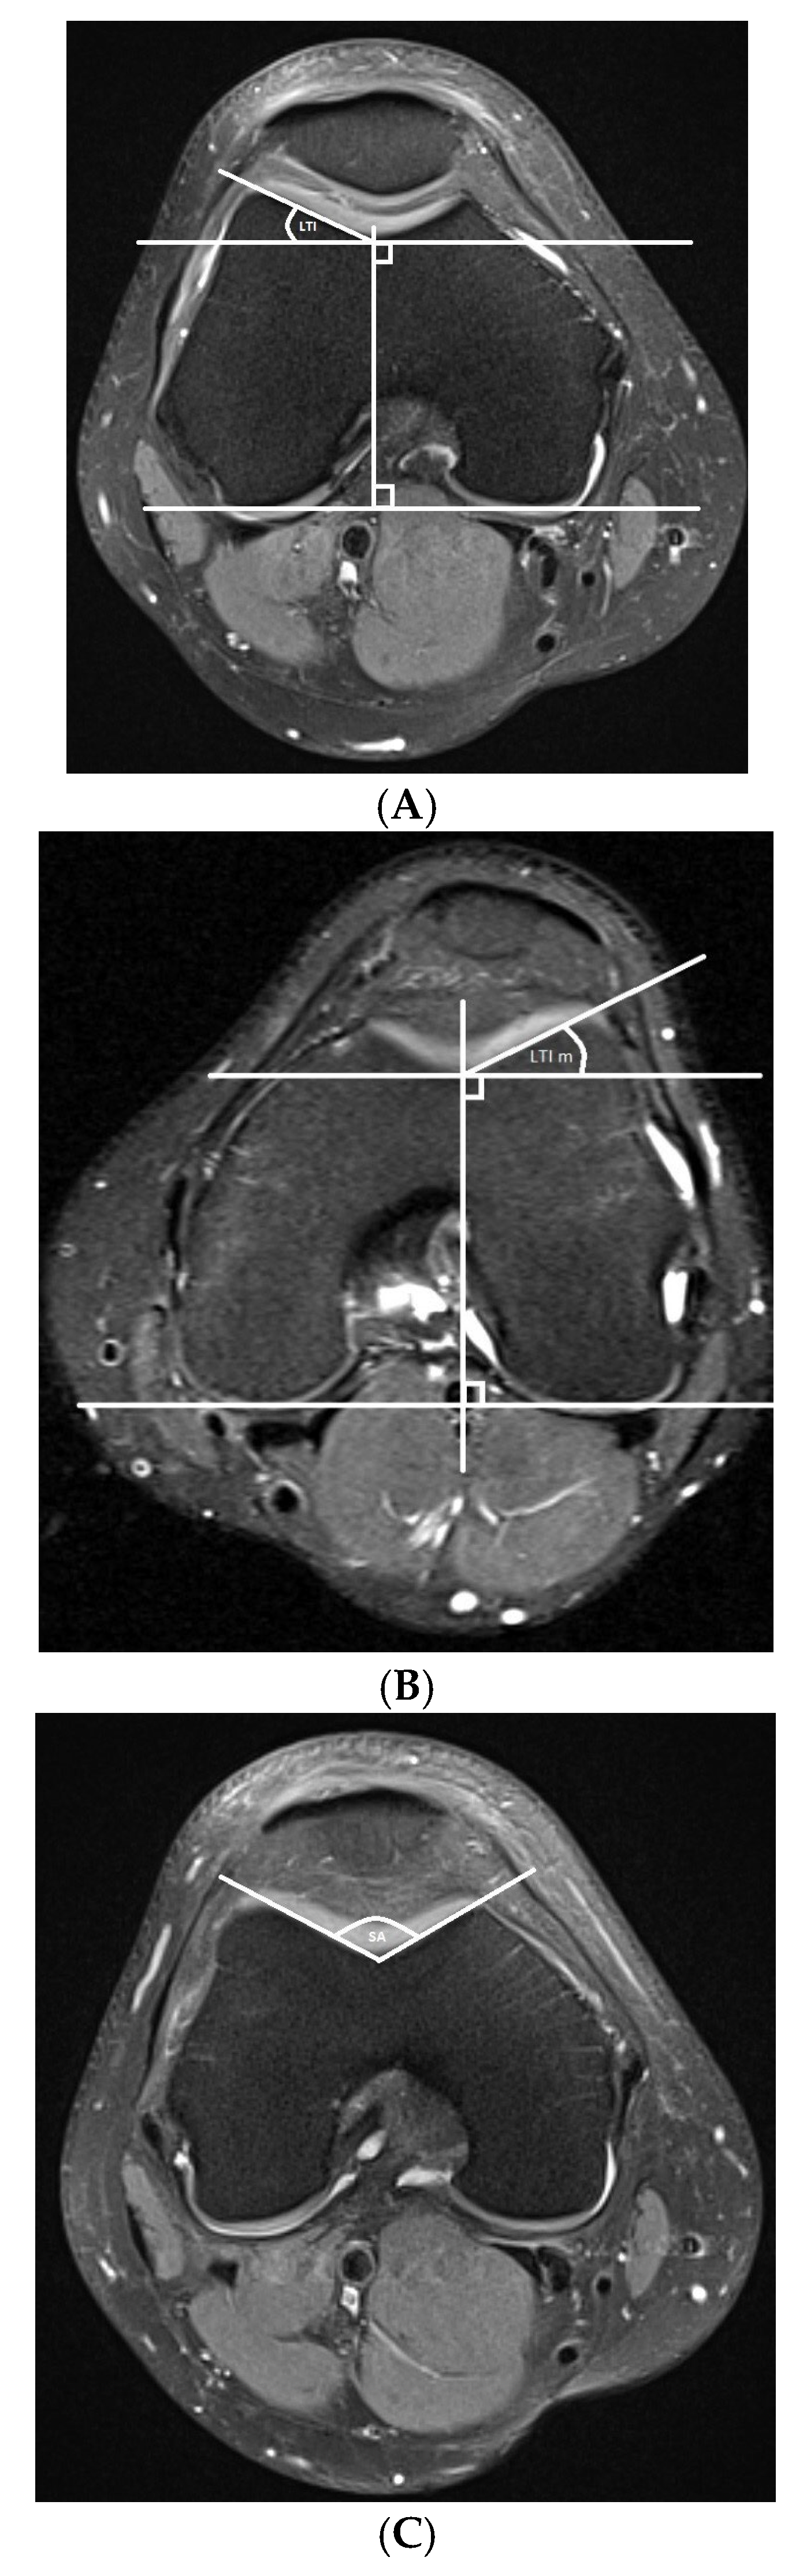

- Trochlear dysplasia measurements